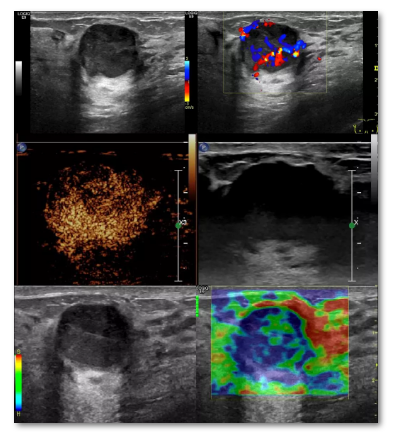

具有良好的软组织分辨力,能够清晰显示乳房及胸壁各层结构,特别是对致密型乳腺,超声检查能够发现毫米级别的小肿块,并确定病变的解剖部位和层次。乳腺超声与X线优势互补,现已成为国际普遍认可的乳腺影像检查的“黄金组合”。

超声检查操作简便易行、且无辐射损害,可以短期多次反复进行,适用于任何年龄和女性任何生理时期(包括妊娠期和哺乳期)。随着科技的发展与进步,超声检查不仅可实时观察病灶二维灰阶超声特征,还具有彩色多普勒血流成像、弹性成像、超声造影等多种新技术,为诊断提供更多依据。